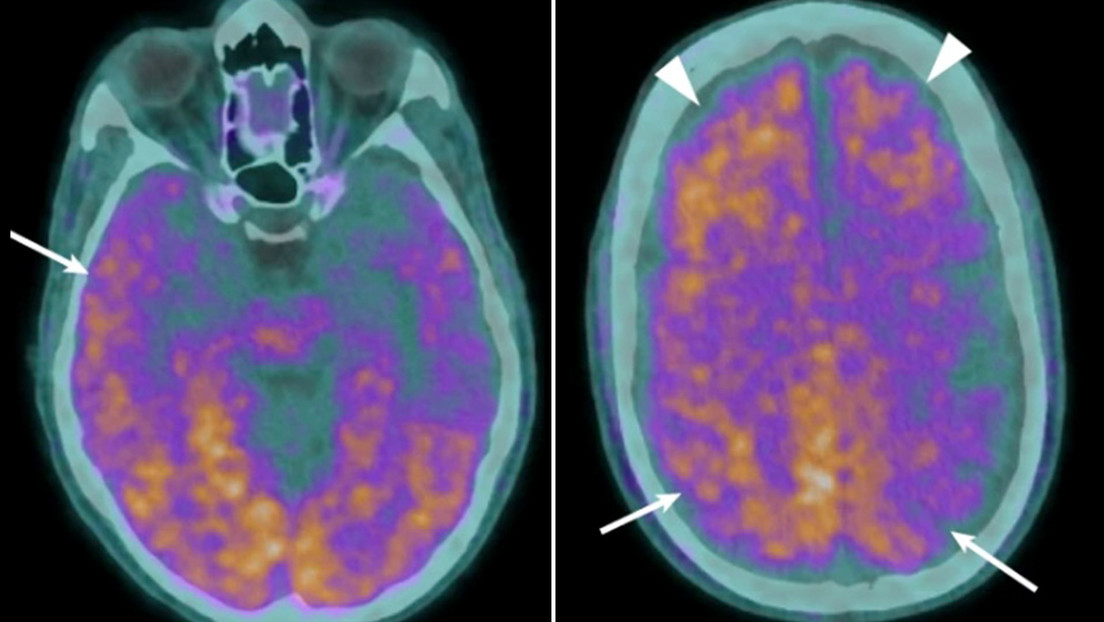

Una mujer brasileña gesta durante más de 50 años a un ‘bebé de piedra’

Una ciudadana brasileña llevaba gestando a un feto calcificado durante 56 años, informó este martes G1, citando a Patrick Derzi, secretario de Salud de la ciudad de Punta Porá, en el estado de Mato Grosso del Sur. La… Read More